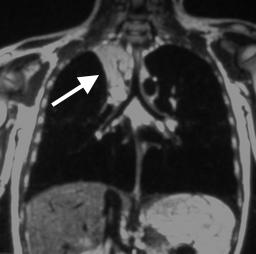

MAGNETIC REASONANCE IMAGING (MRI)

Atelectasis can also be visualized on an MRI

Some key features to keep in mind for the appearance of atelectasis on an MRI are:

- Presence of signal: fundamentally the collapse of this lung parenchyma will appear over a portion of the lung field. On an MRI this will show up as an increased signal (specific type of signal will depend on the type of study).